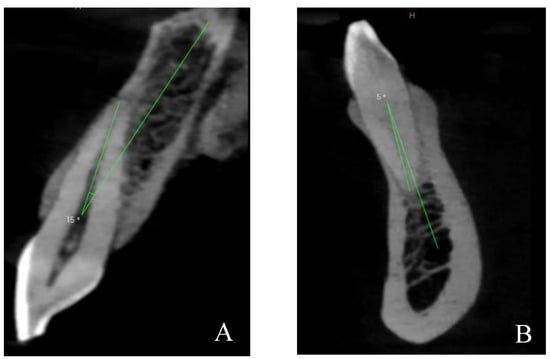

2.4. CBCT Measurements